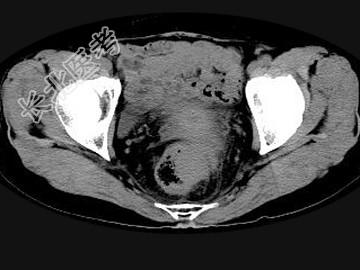

- 单项选择题男,56岁, 排便形状改变,便后不尽感, CT检查如图所示,下列说法正确的是 ( )

A、肠壁上有蒂状新生物

B、其表面光滑,边界清楚

C、肠腔未见狭窄

D、此为直肠息肉

E、此为直肠癌